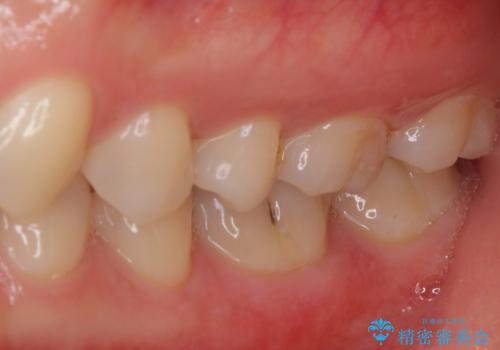

- 奥歯の銀歯と虫歯を気にして来院された患者様です。

下顎は口を開けたときに目立つためセラミックインレーに、上顎奥歯は機能面を優先してゴールドインレーにて修復治療を行うこととしました。

機能面を優先すると、PGAインレー(ゴールドインレー)による修復治療やPGAクラウンによる補綴治療が望ましいのですが、笑ったときに見えている銀歯がどうしても気なってしまうとのことで、目立ってしまう奥歯はセラミックインレーやセラミッククラウンを装着することとしました。